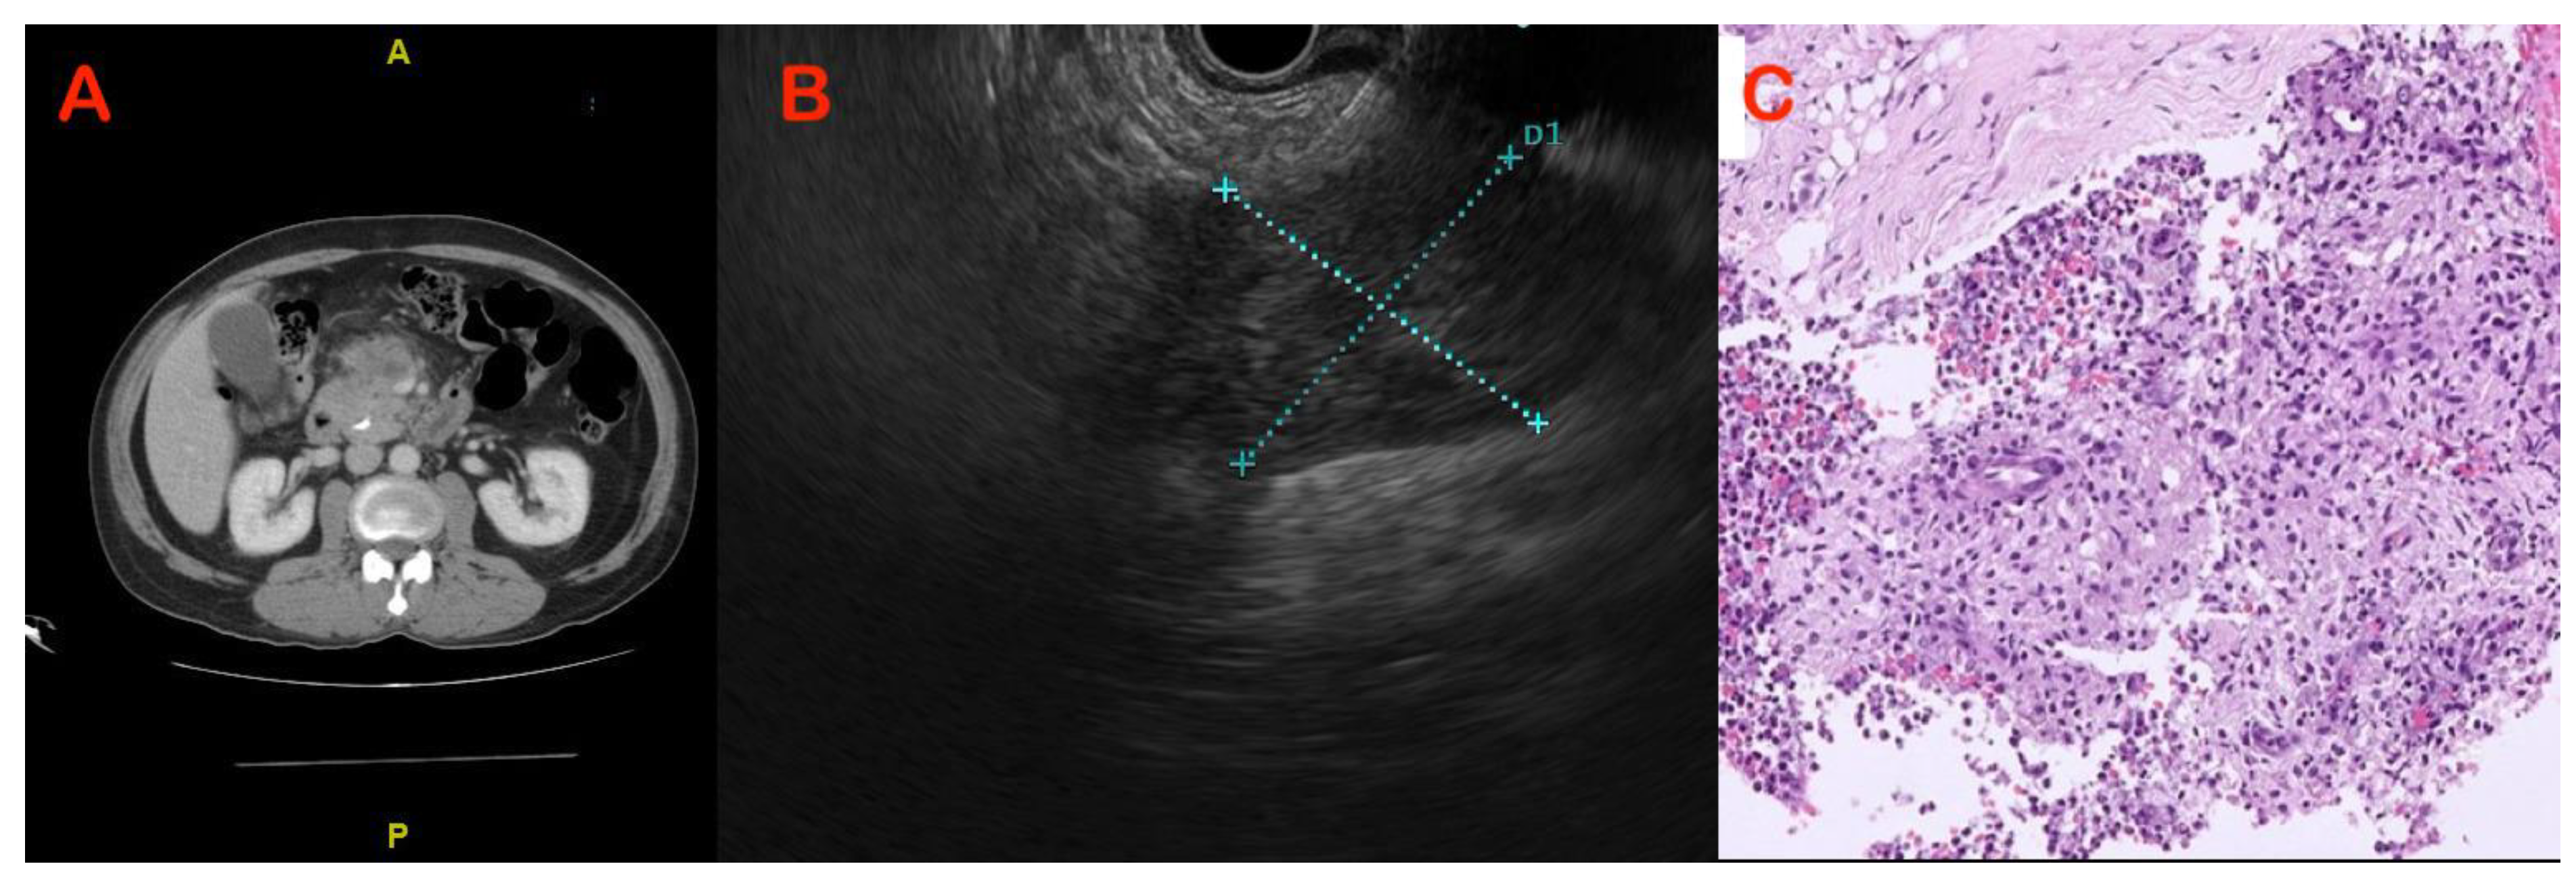

5.3. Endoscopic Modalities